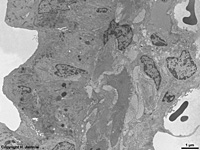

Miniaturbildübersicht Lunge (Pulmo):

Alveolen und Kapillaren

(Ratte)

Alveolen (Lungenbläschen; Terminologia histologica: Alveoli pulmonis; englisch: pulmonary alveols) sind die ca. 0,25 mm weiten Endstücke der Luftwege und der Ort, wo der Atemgasaustausch überwiegend stattfindet. Die einzelnen Alveolen werden durch Alveolarsepten (Terminologia histologica: Septa interalveolaria; englisch: interalveolar septa) voneinander getrennt, die gelegentlich durch offene Bereiche (Terminologia histologica: Pori septales; englisch: alveolar pores) unterbrochen sind. Die im Bereich der Septen gelegenen Zellen, die den Zelltypen der Alveolen selbst entsprechen werden auch als Septumzellen (Terminologia histologica: Cellulae septales; englisch: septum cells) zusammengefaßt. Man unterscheidet innerhalb der Alveolen hier noch einen etwas engeren Eingangsbereich (Terminologia histologica: Atrium alveolare; englisch: alveolar atrium) von dem sackartigen Hauptteil (Terminologia histologica: Sacculus alveolaris; englisch: alveolar saccule). Die Lungenbläschen werden von einem einsichtigen platten Epithel (Terminologia histologica: Epithelium alveolare; englisch: alveolar epithelium) ausgekleidet, welches überwiegend von den Alveolarepithelzellen vom Typ 1 gebildet wird und fast nur in Nischen, die daher auch Nischenzellen genannten, Alveolarepithelzellen vom Typ 2 zeigt.

Unter dem Epithel der Alveolen liegt eine nur sehr dünne Basallamina gefolgt von etwas lockerem Bindegewebe mit einigen elastischen (Terminologia histologica: Fibrae elasticae; englisch: elastic fibres) und kollagenen Fasern (Terminologia histologica: Fibrae collageni; englisch: collagen fibres) sowie nur selten anzutreffenden Fibrozyten. Hauptsächlich wird dieser Raum jedoch von unzähligen Blutkapillaren mit ihren nicht fenestrierten Endothelzellen beansprucht.